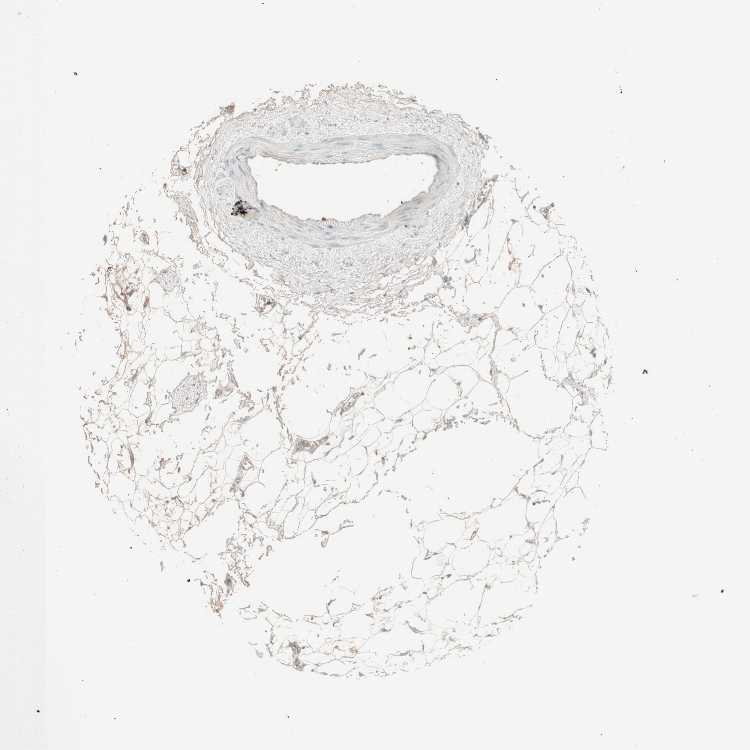

ADIPOSE TISSUE - Antibody stainingi

Antibody staining in the annotated cell types in the current human tissue is reported as not detected, low, medium, or high, based on conventional immunohistochemistry profiling in selected tissues. This score is based on the combination of the staining intensity and fraction of stained cells.

Each image is clickable and will lead to virtual microscopy that enables deeper exploration of all samples and also displays staining intensity scores, fraction scores and subcellular localization as well as patient and tissue information for each sample.

Antibody CAB010344

Adipocytes Low